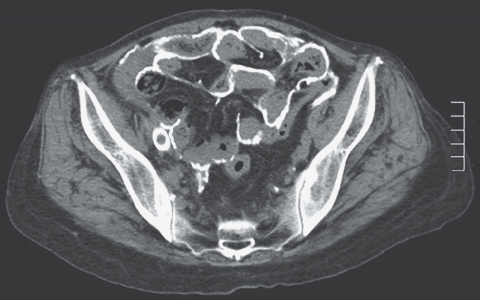

A 54-year-old man is admitted to the ICU after presenting with lowerbackpain(下肢疼痛) radiating to the abdomen, sudden weakness of his lower extremities(末端), hypertension (210/105 mm Hg) and tachycardia(心动过速) (heart rate 113 beats/min). Contrast CT of chest and abdomen shows acute type B thoracic aortic dissection(胸主动脉夹层) extending into the abdomen with occlusion(闭塞) of the abdominal aorta below the level of the celiac(腹腔) artery. He undergoes transthoracic endovascular repair(主动脉夹层腔内修复术). A spinal catheter is placed in the lumbar region before induction of general anesthesia(麻醉). At the end of the procedure he develops a wide-complex arrhythmia with elevated T waves subsequently followed by ST elevations in leads II and V and is quickly returned to the ICU for further treatment.

患者表现为腿部无力,作为远端脊髓急性缺血的替代指标。初始CT显示腹腔动脉下方主动脉血流中断。缺血细胞将钾释放到细胞外,同时伴有潜在的重度代谢性酸中毒。尽管代谢性酸中毒通过钾从细胞内到细胞外的跨细胞转移反复被认为是高钾血症的致病因素,但这种模式受到了挑战。钾的显著升高继发于腹腔动脉远端的再灌注,这解释了广泛复杂心律失常、T波峰值/ST段抬高和最终心搏停止的发生。